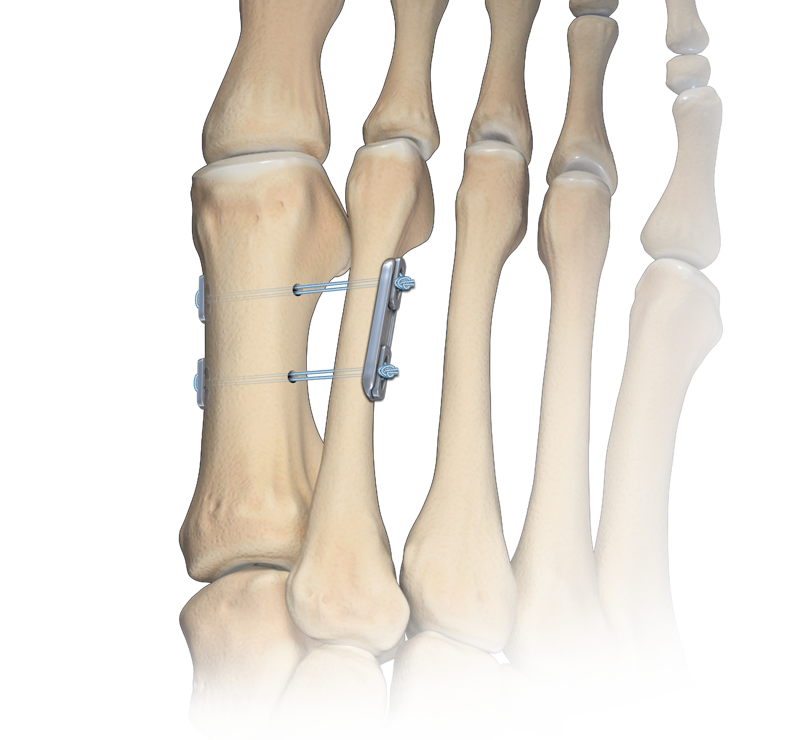

Рентген после операции Hallux valgus